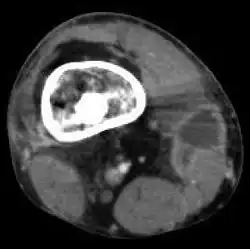

Mycobacterium doricum osteomyelitis and soft tissue infection. Computed tomography scan of the right lower extremity of a 21-year-old patient, showing abscess formation adjacent to nonunion of a right femur fracture.

Extensive osteomyelitis of the forefoot